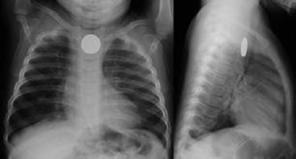

How is a swallowed button battery diagnosed?

Your child may need to have an x -ray of the appropriate area to locate the battery.

Are button batteries dangerous?

Swallowing any button battery, old or new, can cause life threatening injuries and even death, especially if it becomes stuck in the oesophagus (food pipe). Batteries which become stuck in the nose or ears can also cause local burns.

When swallowed, the left over electrical current in a button battery reacts with moisture to produce a strong alkali chemical. The chemical can cause serious internal burns and bleeding. The batteries can also leak chemicals which can cause serious burns. The coin shaped batteries are easily caught in the oesophagus, and when stuck can start to cause damage very quickly (within 2 hours). There may be no early symptoms.

Who is at risk?

Young children are at most risk of poisoning from button battery ingestion. Young children are curious and like to explore by putting everything in their mouth. This leads to more accidental ingestions. A toddler’s smaller body size also means they are more likely to have a button battery caught in the oesophagus, causing serious damage. How is a swallowed button battery diagnosed? Your child may need to have an x-ray of the appropriate area to locate the battery.